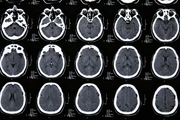

При подозрении на инсульт, пациент должен быть срочно госпитализирован и обследован. В диагностике обычно используется компьютерная томография, магнитно-резонансная томография. При отсутствии возможности проведения этих методов, диагностика менее достоверна и является результатом анализа клинической картины, данных спинномозговой пункции (в ликворе присутствует кровь), эхоэнцефалоскопии, дуплексного сканирования и церебральной ангиографии. Также необходимо исследовать: электролиты сыворотки крови, показатели функции почек, ЭКГ, маркеры ишемии миокарда, клинический анализ крови, протромбиновый индекс, насыщение крови кислородом.

Медицинские процедуры, проводимые при заболевании инсульт: Спиральная компьютерная томография, Магнитно-резонансная томография, Биохимический анализ крови, Клинический анализ крови, ЭКГ, Рентген, Спинальная пункция, Эхоэнцефалография, Дуплексное сканирование брахиоцефальных артерий (БЦА), Ангиография, Протромбиновое время, Протромбиновый индекс, Исследование газов крови